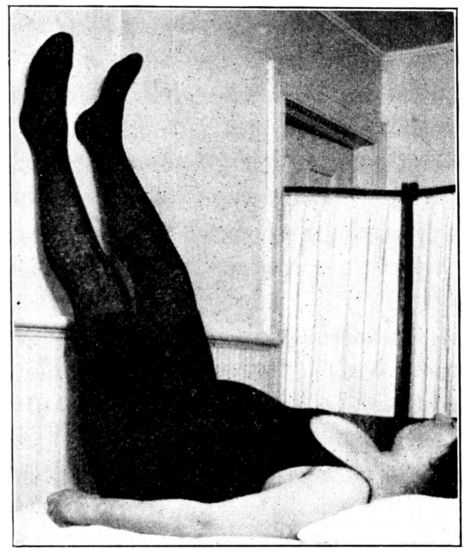

| 40. | Patient in right-angled position to relieve varicose veins | 138 |

| 41. | Elevated Sims position | 139 |